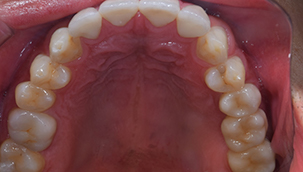

奥歯の詰め物の治療終了後

奥歯の治療が終わったところです。前歯の治療に行く前に、噛み合わせをしっかり確認します。

全ての治療終了後

前歯の治療が終わったところです。前歯は全く違和感がなく入っています。

治療後

全体の治療前後

銀歯の主張がなくなり、とても自然になりました。見た目もそうですが、雰囲気や第一印象もかなり変わりました。